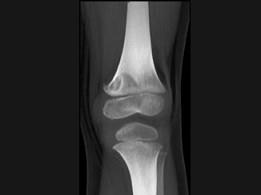

问题 男,12岁,大腿下部间歇性疼痛,劳累后加重,结合图像,最可能的诊断是 ( )

选项 A、邻皮质软骨瘤 B、非骨化性纤维瘤 C、干骺端结核 D、骨样骨瘤 E、纤维性骨皮质缺损

答案 E